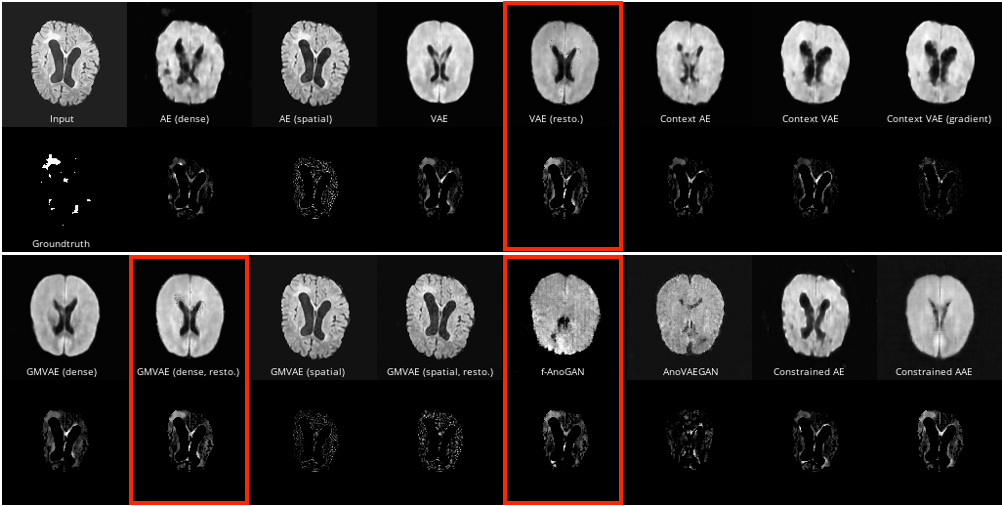

The results in Section 4 show that a simple baseline can outperform or compete with even the strongest related Machine Learning (ML) techniques. These findings challenge the effectiveness of current ML approaches for SAS. The results of Baur et al. [4] also show that DSC does not correlate well with reconstruction quality. Especially, one can see in Figure 4, that the best performing models (VAE with restoration, dense GMVAE with restoration, and f-AnoGAN) produce very textureless reconstructions. They can detect the largest connected anomaly located at the dorsal aspect of the right lateral ventricle (note that the images are oriented such that the patients’ right ventricle is on the left side of the image) only because it is hyperintense in the input image. We refer to the original paper for a higher-resolution version of this figure. Hence, we hypothesize that the models in Baur et al. [4] do not perform anomaly segmentation by learning the normal anatomy of the data, but that the necessary information to perform anomaly segmentation with the performance presented in our work is already present in the input image. The quantitative evaluation of our experiments indicates that using the residual between the model output and the input image actually degrades the segmentation quality of the resulting anomaly map.